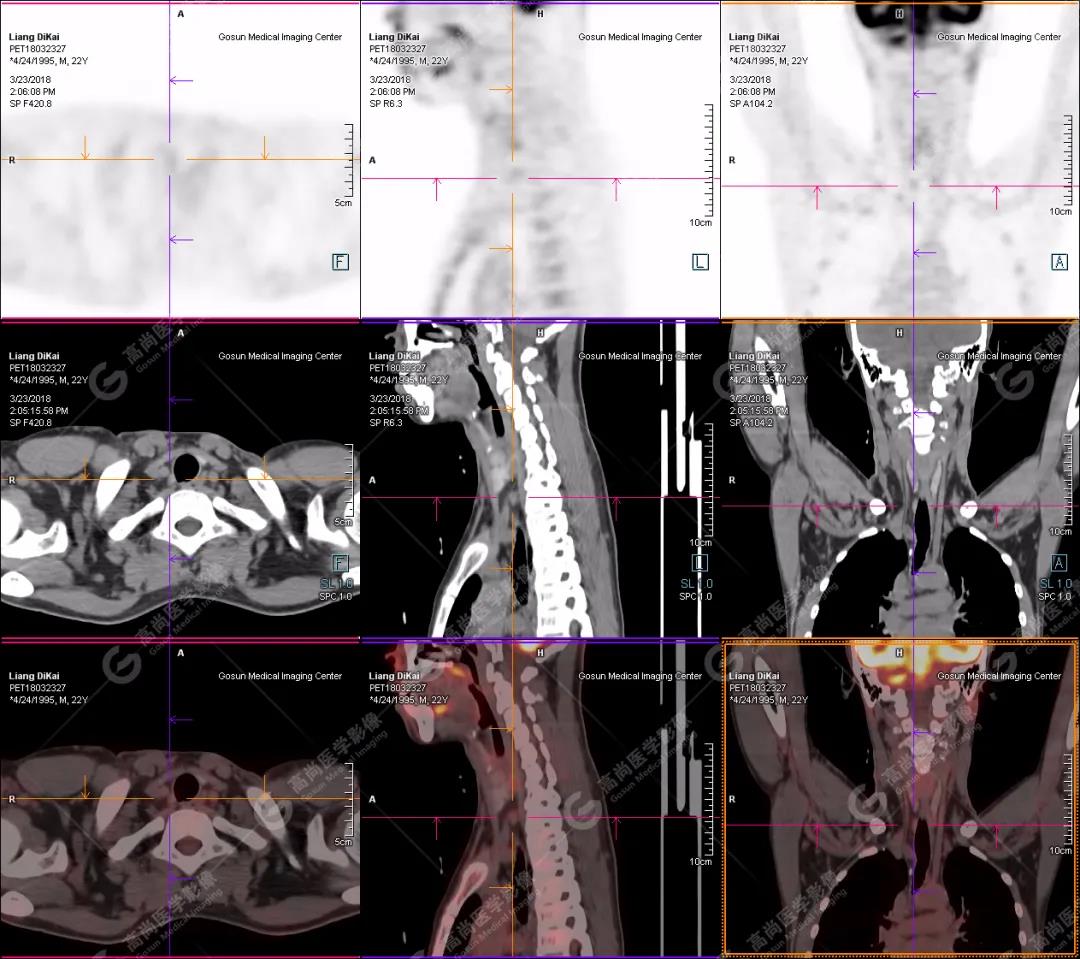

本中心PET/CT提示

1.右肘關(guān)節(jié)周圍、骶尾部皮下、雙側(cè)臀部、盆腔左側(cè)壁及左側(cè)大腿根部肌肉、肌間隙多發(fā)結(jié)節(jié)狀、片塊狀及不規(guī)則巨塊狀高密度鈣化灶,伴代謝不均勻輕度增高,考慮為鈣質(zhì)沉著癥;

2.甲狀腺雙葉后方多發(fā)(右2個,左1個)小結(jié)節(jié)狀軟組織影,部分代謝輕度增高,多考慮為甲狀旁腺腺瘤。